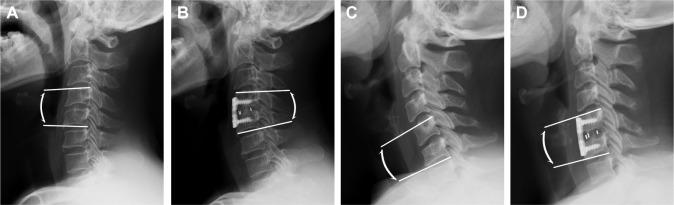

We retrospectively reviewed patients who underwent single-level ACDF surgery in our hospital between January 2014 and February 2017. Basic characteristics of patients included age at surgery, gender, diagnosis, duration of symptoms, and location of target level. Pre- and postoperative radiographs at the 6-month follow-up were used to evaluate the following parameters, such as segmental angle, C2-C7 angle, T1 slope, and C2-C7 sagittal vertical axis (SVA). Postoperative clinical outcomes were assessed by the Neck Disability Index and VAS. According to the segmental angle of postoperative radiographs, patients were divided into noncorrection group and correction group.

A total of 181 patients (99 males and 82 females) were analyzed in our study. There were 32 patients in the noncorrection group and 149 patients in the correction group. There was no significant difference in demographic and clinical data between the two groups before surgery. However, patients in the correction group showed larger C2-C7 angle and lower C2-C7 SVA after surgery in comparison with those in the noncorrection group. Besides, changes in the segmental angle were positively correlated with changes in C2-C7 angle and negatively correlated with changes in C2-C7 SVA.